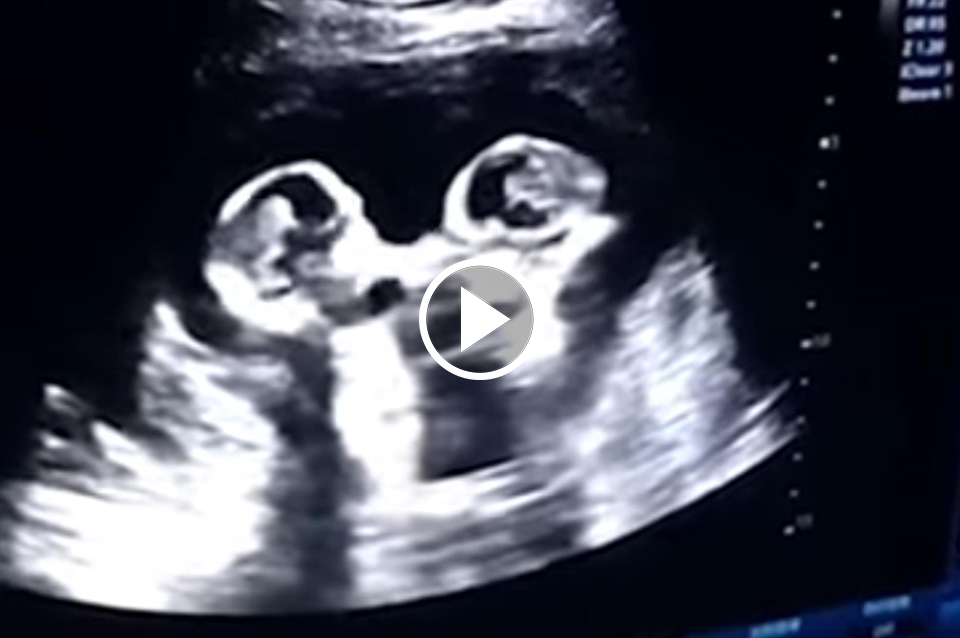

Una ecografía captura a dos gemelas peleando en el útero de su madre

La ecografía de una mujer embarazada de cuatro meses donde se aprecia a dos gemelas que aparentemente se están golpeando entre sí dentro del útero de la madre. Las pequeñas compartían saco amniótico y placenta.

El clip de ultrasonido muestra que las pequeñas se encuentran cara a cara y luego, de repente, parecen golpearse entre sí. Sin embargo, cuatro meses después las gemelas nacieron sanas en un hospital en Yinchuan, China. Según han explicado a varios medios locales el director del hospital en Yinchuan:

El caso podía ser peligroso porque se supone que las gemelas están creciendo en la misma ‘habitación’ cuando normalmente los gemelos se desarrollan en dos. Por esta razón sucede una vez cada 60.000 casos.

Conocidos como gemelos monoamnióticos monocoriales o gemelos Mo-Mo, se trata de uno los embarazos de gemelos de mayor riesgo. De hecho, solo hay un 50% de probabilidades de que los bebés sobrevivan después de las 26 semanas. Por fortuna, estas dos hermanas que apuntan maneras de luchadoras nacieron sin complicaciones.